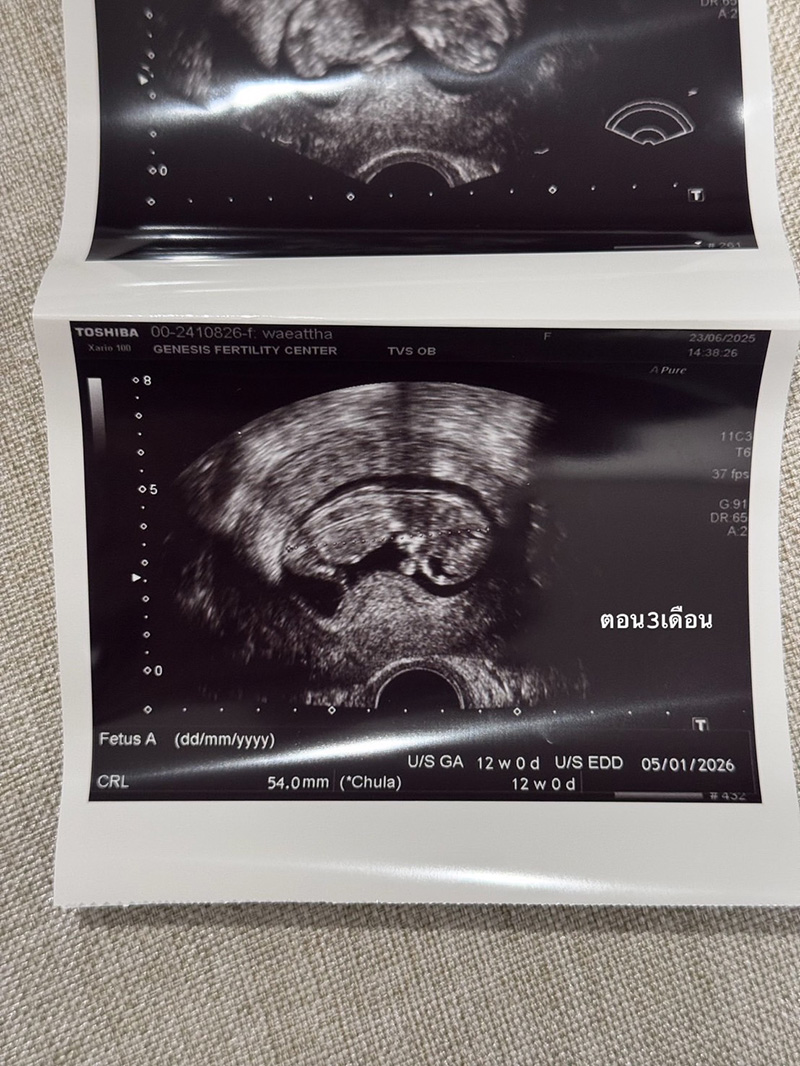

ช่วงนี้หาย ๆ ไปเพราะว่าเนยมีน้องแล้ว ในรูปคือประมาณ 3 เดือนตอนนี้ก็เกือบจะ 4 เดือนแล้ว ท้องป่องแล้ว ต้องบอกว่าจะมีลูกคนนึงไม่ง่ายเลยเข้าใจว่าตัวเองแข็งแรงสุขภาพดีมาก ดูแลตัวเองมาอย่างดีมาก ๆ อาหารการกินคือคลีน ไม่ดื่ม ออกกำลังกายสม่ำเสมอ นอนไม่ดึก แต่ปรากฏว่า เนยบ้ายบายน้องไปถึง 2 รอบ จนแปลกใจมากจริง ๆ เลยตัดสินใจไปหาคุณหมอมิงค์ ที่ @gfc.bangkok พอตรวจปรากฏว่า เนยละก็สามี มีโรคทางพันธุกรรมแฝงทั้งคู่ (เลยรู้สึกว่าก็โชคดีที่น้องบ้ายบายไปถึง 2 รอบเพราะถ้ารอดมาชีวิตก็คงลำบาก) โอกาสที่เด็กจะออกมาสมบูรณ์มีแค่ 25% เท่านั้น ซึ่ง % ที่เหลือคือเป็นโรคกับเป็นโรคแฝงแบบเนยที่ใช้ชีวิตปกติจนโตได้แต่เราก็จะมียีนที่ผิดปกติติดตัวส่งทอดไปสู่รุ่นอื่น ๆ ได้ ซึ่งเนยเลือกที่จะให้ลูกสมบูรณ์ 100% เลยดีกว่า เลยเริ่มทำ ICIS กับทางคลีนิค ทั้งคัดโครโมโซม ตรวจคัดโรค และหลังใส่ตัวอ่อนก็ทำ NIFTY อีก (คือต้องเพอร์เฟคละมั้ย 555)

สำหรับเนยเป็นการทำ ICIS ครั้งแรกแล้วก็ประสบความสำเร็จเลย ไม่ต้องทำหลาย ๆ รอบให้ท้อใจ ตอนนี้น้องสมบูรณ์แข็งแรงมากแค่ 3 เดือนก็ดิ้นเก่งซะแล้ว ต้องขอบคุณ GFC มาก ๆ ที่ทำให้ทุกอย่างราบรื่นจริง ๆ